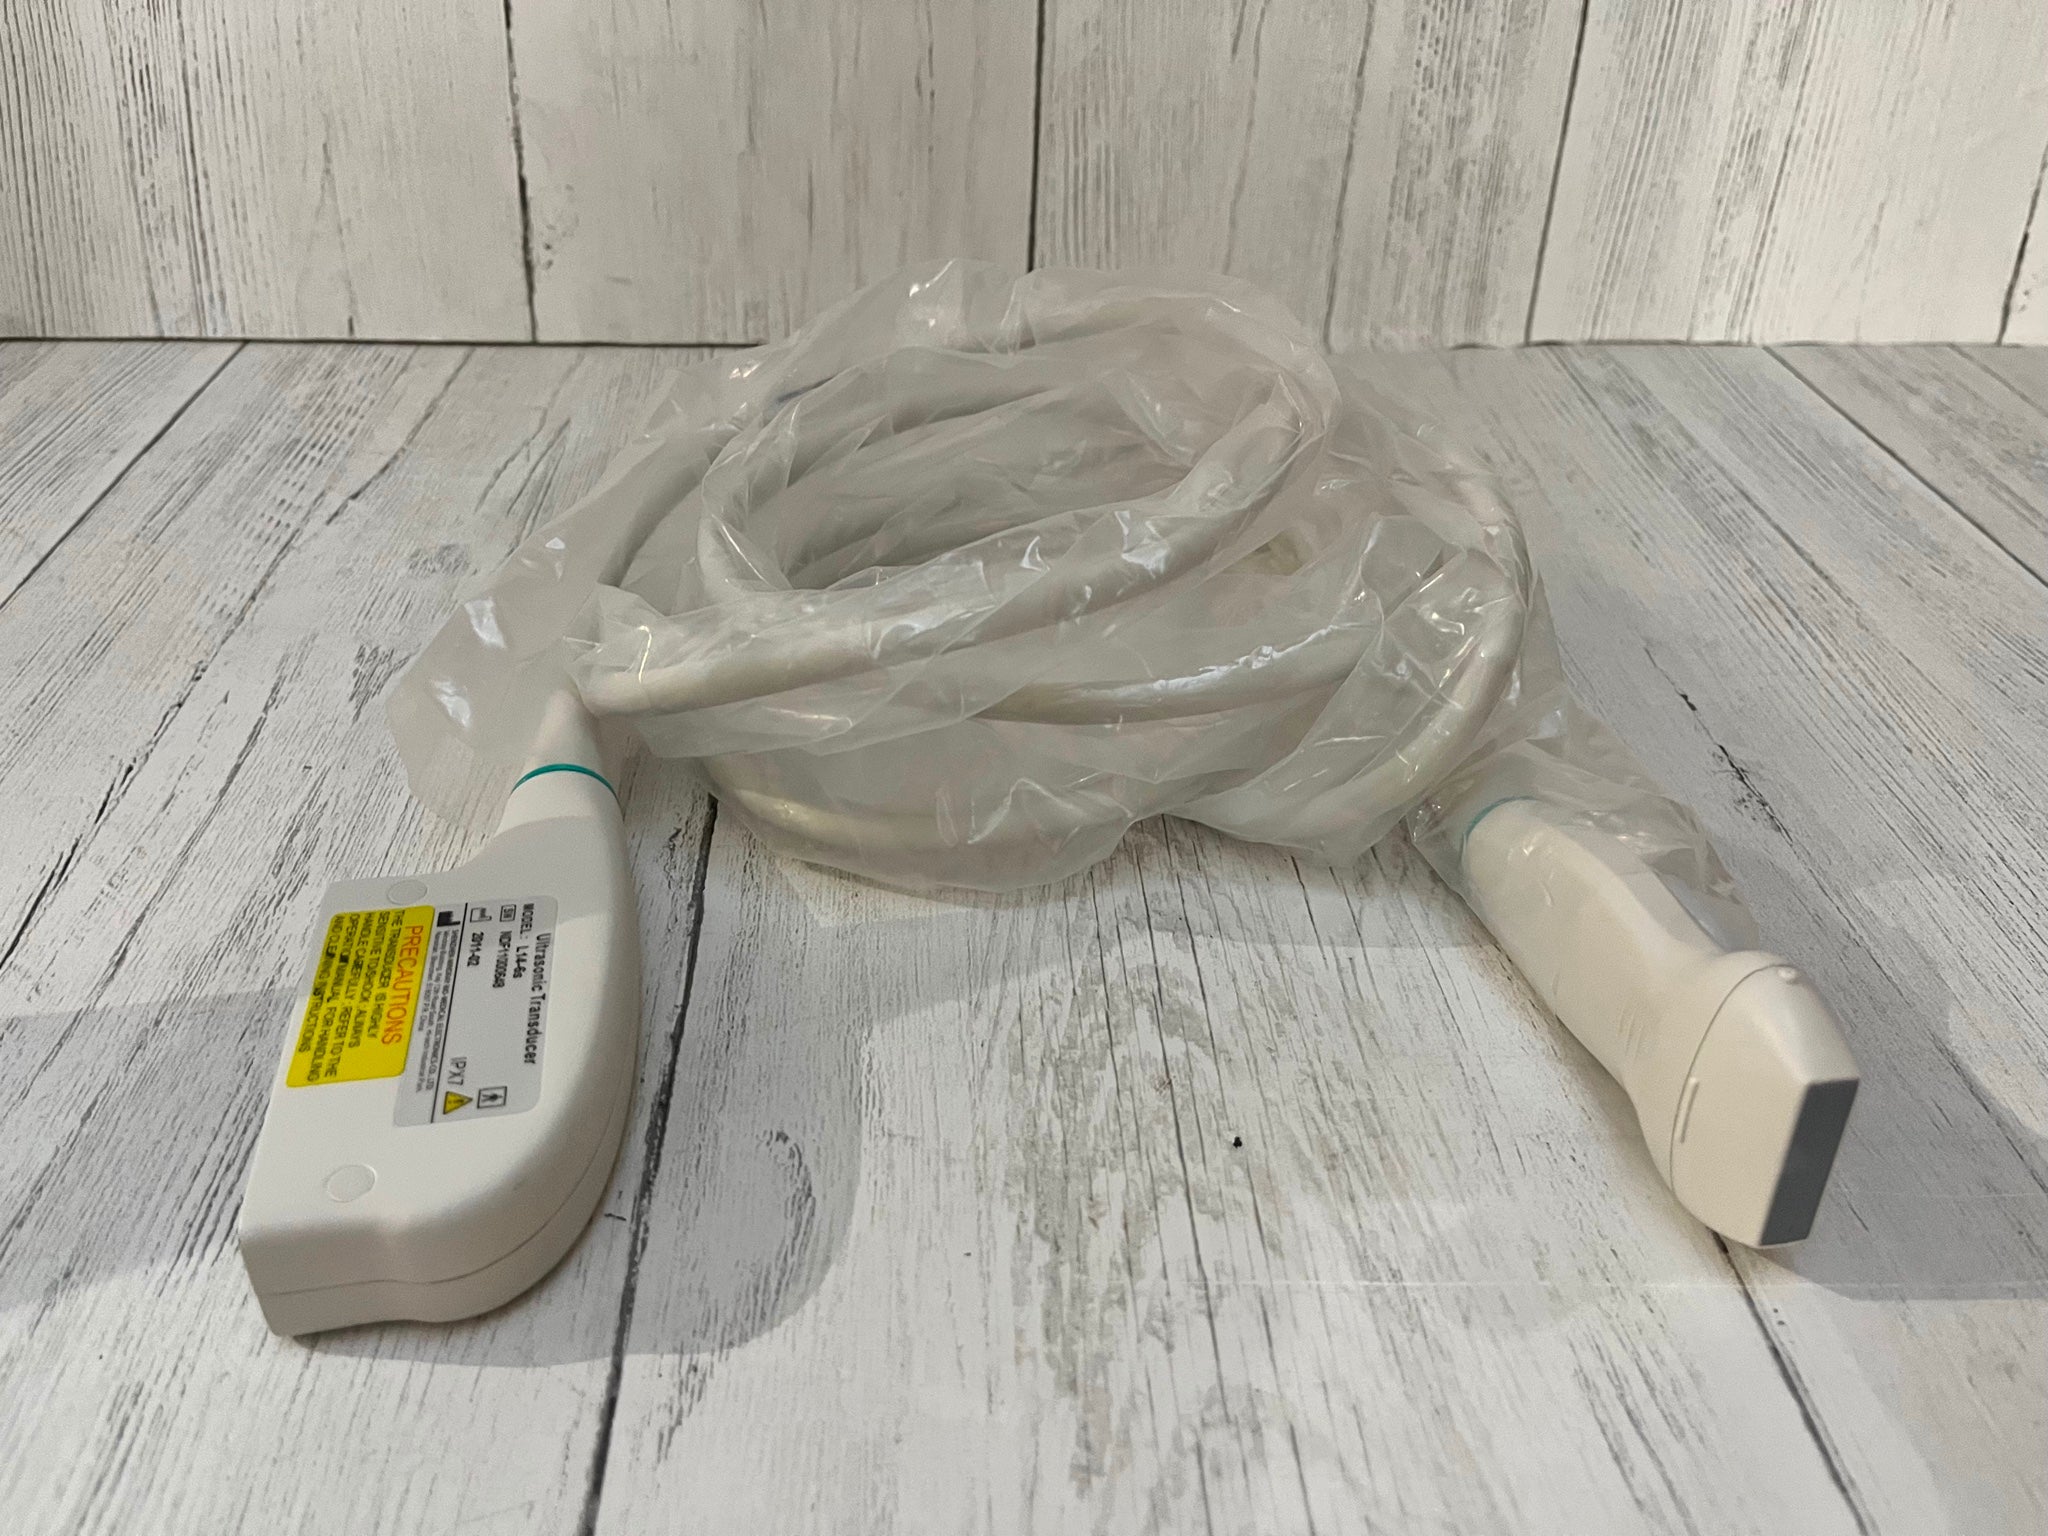

The CE Digital Laptop Ultrasound Machine offers outstanding imaging capabilities that are essential for modern diagnostic practices. It features a 6.5MHz Transvaginal probe that provides high-resolution images, enabling healthcare professionals to visualize internal structures with great clarity. This machine is designed to help in various examinations, ensuring better accuracy and improved patient care.